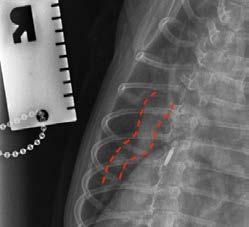

Conscious thoracic radiographs were taken, which highlight the very dilated and tortuous pulmonary lobar arteries in the lateral and dorsoventral views (credit to Dr Catheryn Walsh), consistent with heartworm infection. Cardiomegaly was appreciated; however, the left atrium did not appear obviously enlarged on radiographs and there was no obvious interstitial to alveolar pattern consistent with left-sided congestive heart failure.

Figure 4. Tortuous pulmonary artery on lateral view